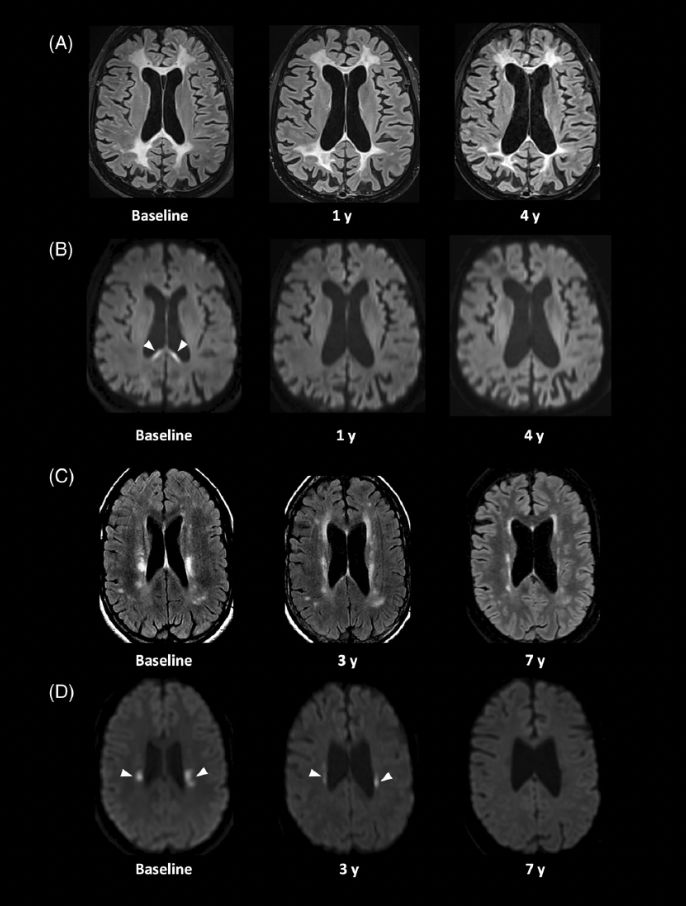

Post image Post image

Exciting results from Yska et al.: Hematopoietic stem cell transplantation halted disease progression in CSF1R-related disorder after 6 months post-transplantation, with impressive clinical and radiological improvements at a median follow-up of 2.5 years. https://loom.ly/SE3UXUE